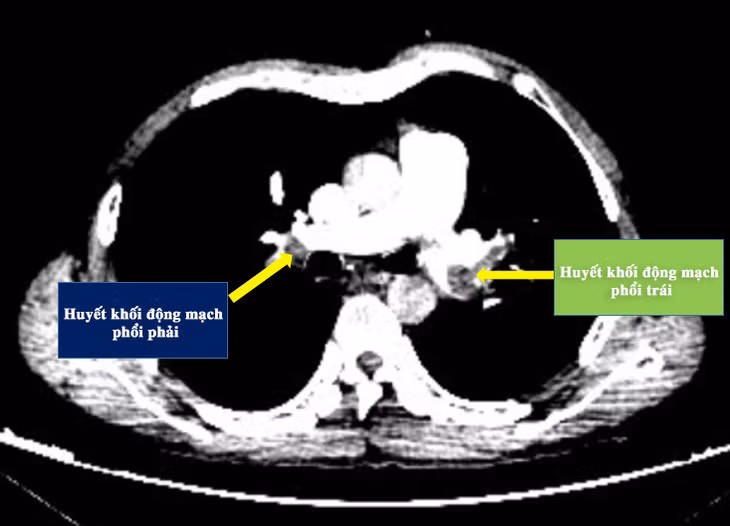

Bệnh nhân được xử trí cấp cứu duy trì thuốc chống đông, vận mạch và lập tức chuyển lên Bệnh viện tỉnh. Bệnh nhân được chụp cắt lớp vi tính dựng hình mạch phổi phát hiện tình trạng tắc động mạch phổi hai bên.